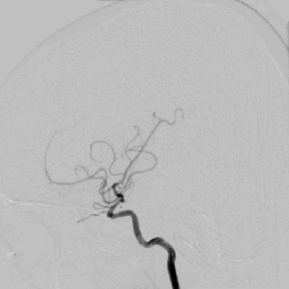

5、 术后正侧位造影及3D造影

多角度投照显示支架帖壁良好,远端血管显影好,前向血流mTICI3级。

3D:左侧颈内动脉C7段中度狭窄,左侧大脑中动脉M1段重度狭窄。